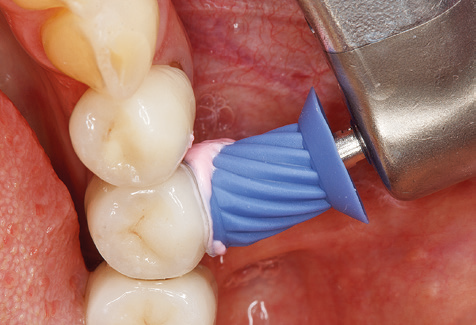

Good illumination of the working field facilitates the process considerably. The system used by the authors achieves this thanks to a 5x LED ring integrated in the handpiece. Naturally, a range of working tips for different indications is also offered. A straight, universally employable tip is the basic instrument required for machine cleaning of natural teeth (Fig. 5a and b). Curved tips, which allow access to exposed furcations, are also available for hard-to-reach areas in the posterior region (Fig. 6).

Of course, working tips for the cleaning of implant surfaces are also indispensable for SPT in patients fitted with implants. The implant cleaning attachment on the system used here is characterised by its tapered, hexagonal design. This design allows light, atraumatic penetration of the peri-implant pocket and displays a good cleaning performance (Fig. 7).

Following machine cleaning of the tooth and implant surfaces, the surfaces of the natural teeth are cleaned manually using standard hand instruments. When performing manual cleaning, particular attention must be given to maintaining the correct angle of application, appropriate sharpness, good support and working with the curette from apical to coronal. Either titanium or carbon curettes should be used for post-cleaning of the implant structures (Fig. 8). In addition to the use of ultrasonic devices, power jet devices can also be used in conservative dentistry. However, it must be taken into consideration that these procedures are not suitable for removing hard deposits and thus they cannot replace the use of hand instruments and ultrasonic instruments completely. In all cases, cleaning is followed by mechanical polishing of the accessible tooth and implant surfaces with polishing cups and polishing compounds (Fig. 9).

Fig. 4: Flexible probes with millimetre markings are recommended for the probing of dental implants (e.g. Colorvue Kit PCV11KIT6, Hu­Friedy). – Fig. 5a and b: A straight working tip (1P, W&H Dentalwerk Bürmoos GmbH) is a suitable instrument for use on all natural teeth. – Fig. 6: Curved working tips (3Pr/3Pl, W&H Dentalwerk Bürmoos GmbH) lend themselves to the processing of difficult-to-reach areas of the tooth and root surfaces (e.g. furcations). – Fig. 7: The tapered, hexagonal implant cleaning tip (1I, W&H Dentalwerk Bürmoos GmbH) permits atraumatic and efficient cleaning of the crown and abutment surfaces. – Fig. 8: Titanium and carbon curettes are suitable instruments for the manual cleaning of the implant surfaces.